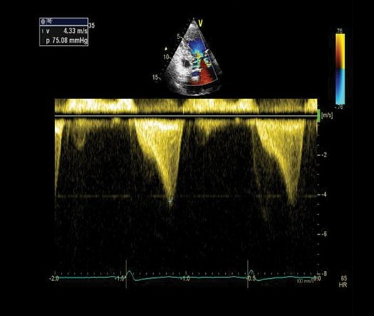

A point-of-care ultrasound was performed to evaluate for potential etiologies of syncope. The ultrasound displayed biventricular and interventricular septal hypertrophy (Figure 2), systolic anterior motion of the mitral valve (SAM, Figure 3), and a “dagger-like” continuous wave Doppler waveform emerging from the left ventricular outflow tract. (LVOT, Figure 4)

Figure 4. Apical 5-chamber view using continuous wave Doppler displaying a “dagger-like” left ventricular outflow obstruction with a maximal peak gradient of 75 mmHg.1

The left ventricular outflow tract (LVOT) gradient is another way bedside ultrasound can be utilized in the diagnosis of obstructive HCM. This is performed by placing the continuous wave Doppler beam over the LVOT in an apical 5-chamber view. A gradient > 30 mmHg is defined as intraventricular obstruction. About 1/3 of patients with HCM have gradients > 30 mmHg at rest, another 1/3 have it with provocation (Valsalva/exercise/medication), and 1/3 have no obstruction.11 In the ED, a Valsalva maneuver is an imperfect (underestimates exercise-induced obstruction) but convenient provocation. Furthermore, a gradient of > 50 mmHg is considered hemodynamically significant, often requiring invasive septal reduction therapies.12 Continuous Doppler images will classically show a “dagger-like,” late-to-rise waveform characteristic of HCM.